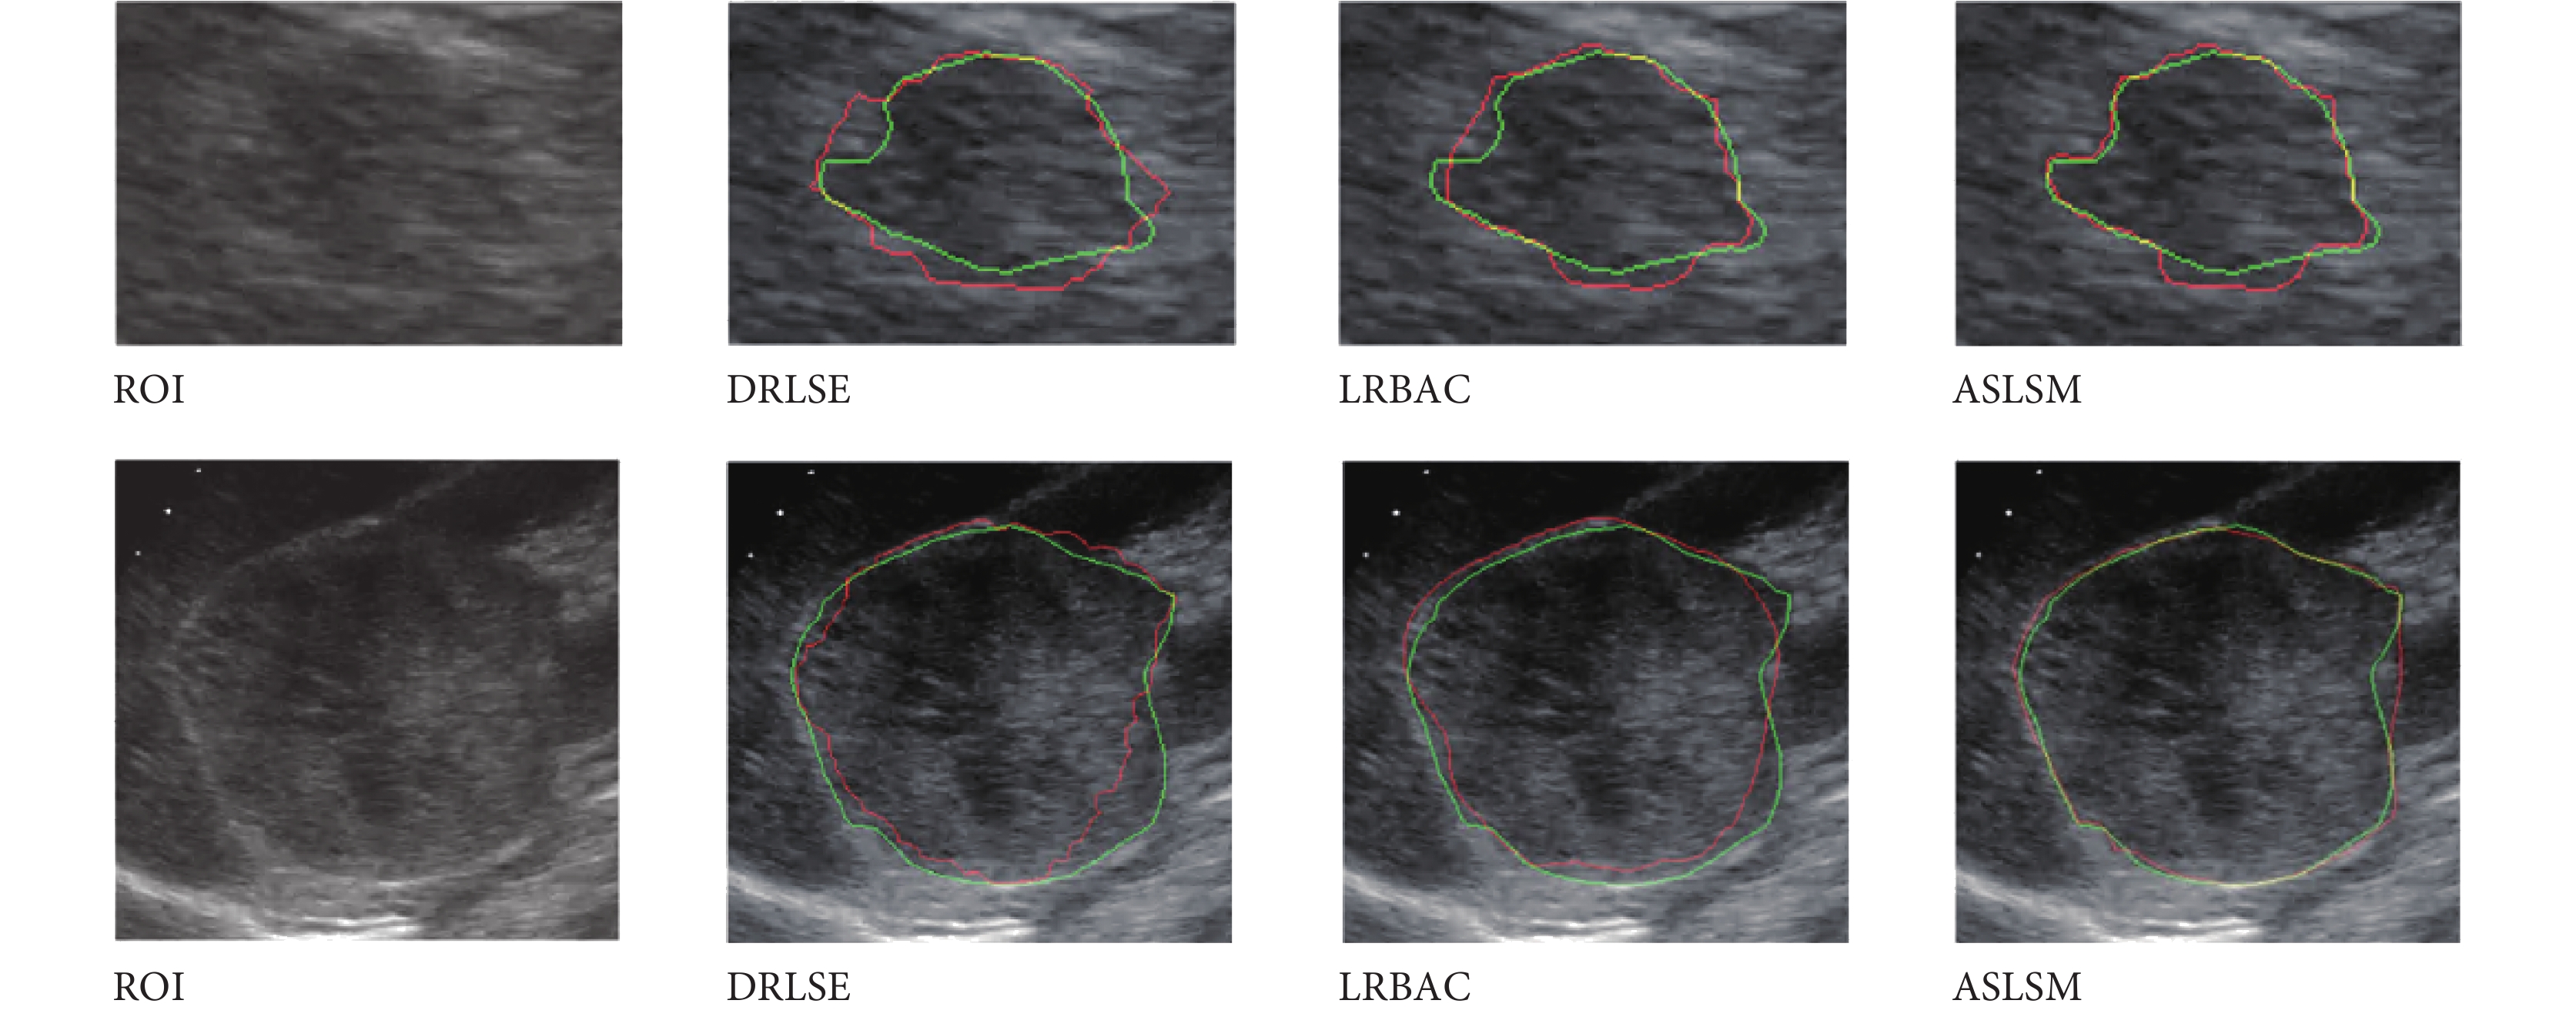

3.7 DRLSE、LRBAC、ASLSM 實驗

DRLSE 僅使用梯度作為驅動項,跨越噪聲能力差,LRBAC 卷積半徑過大丟失細節,過小演化不到真正邊界。ASLSM 通過自適應內外能量和梯度,獲取細節能力明顯增強。本實驗分別使用 DRLSE、LRBAC、ASLSM 分割 261 幅超聲圖像,結果如表 6 所示。ASLSM 犧牲了一定運算時間,效果要明顯好于 DRLSE、LRBAC。如圖 15 所示,綠線為金標準,紅線為分割結果。對應原始的腎臟腫瘤超聲圖像 ROI 區域;DRLSE 結果顯示僅僅使用梯度特征,不能跨越大噪聲區域演化到真正邊界;LRBAC 則過于光滑難以獲取細節,演化不到真正的邊界,而 LRBAC 卷積半徑過小演化不邊界;但采用 ASLSM 自適應 p(i)、convr(i)、q(i),能更加準確演化到真正邊界。